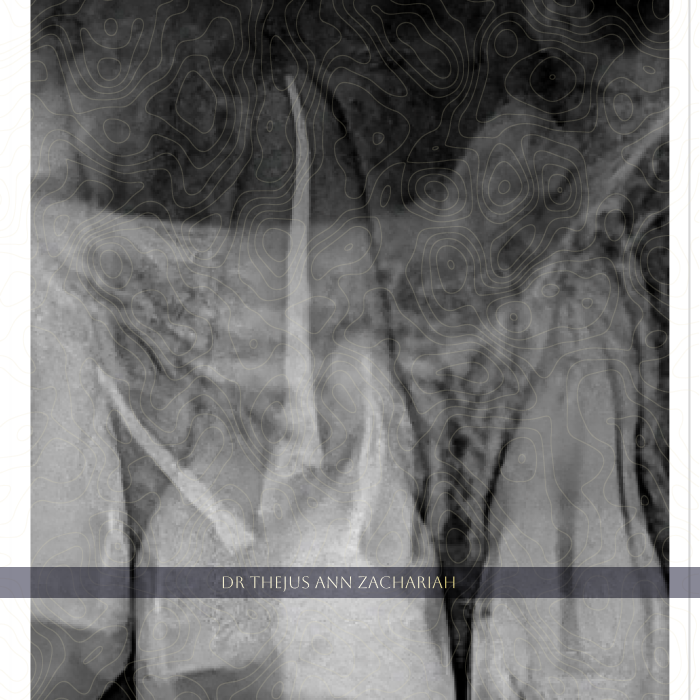

MB2 Negotiation

alt text